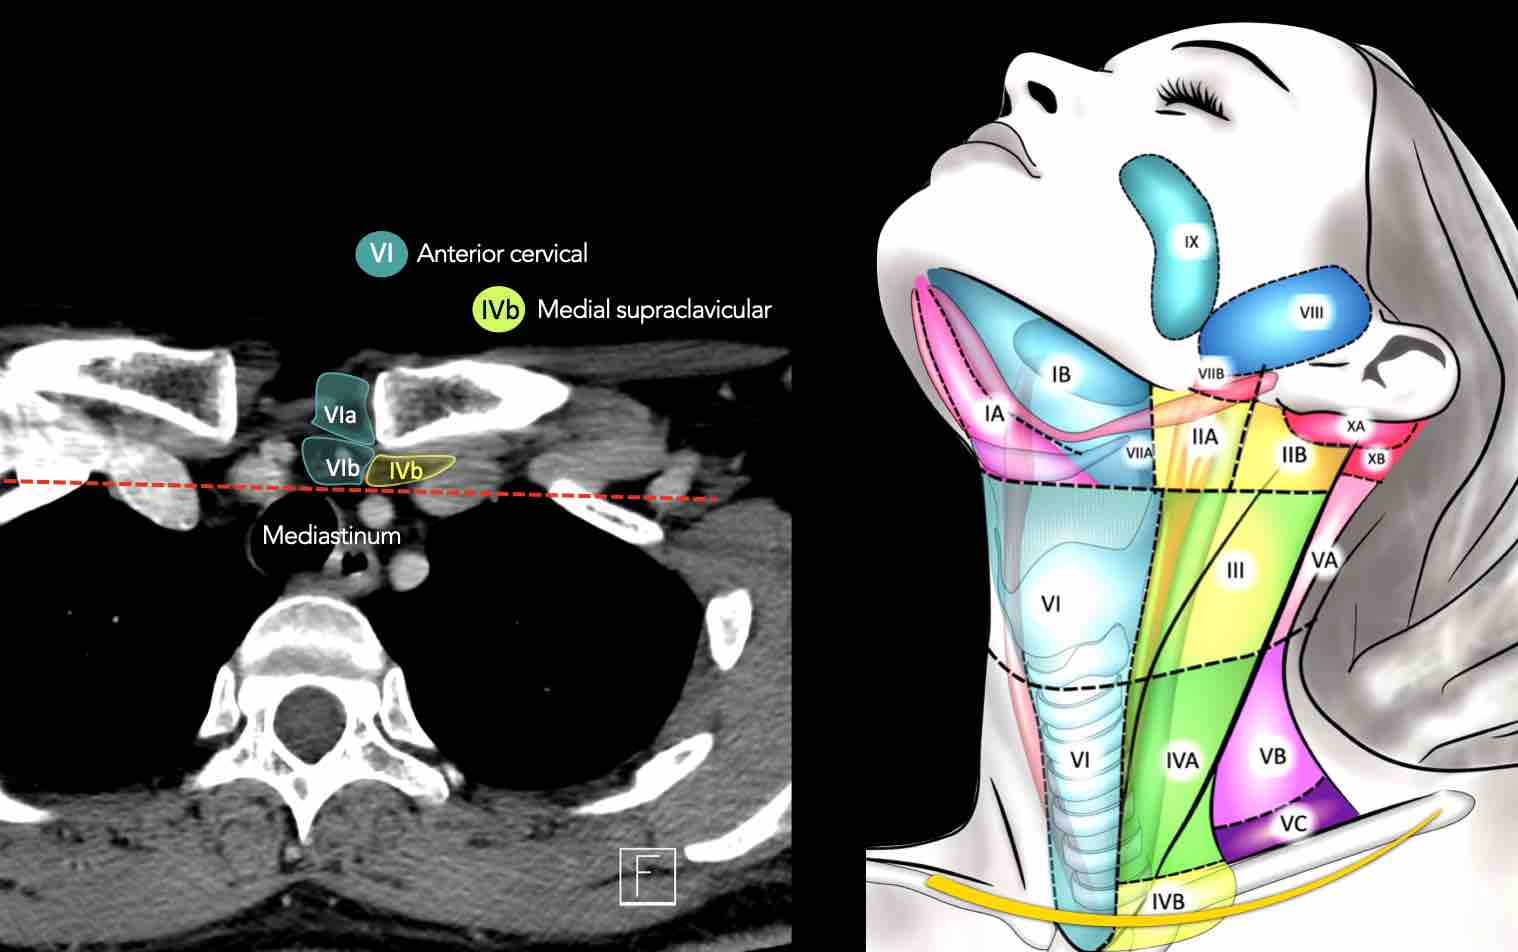

CT Scan Mặt Cắt Ngang (Axial CT)

Các lát cắt CT mặt phẳng ngang tương ứng với hình minh họa tổng quan.

Các lát cắt CT mặt phẳng ngang với hình ảnh chi tiết hơn.

VI – Cổ trước

IV – Tĩnh mạch cảnh dưới và hố thượng đòn trong

Ranh giới giữa tầng IVa và IVb được xác định tùy ý tại vị trí 2 cm phía trên khớp ức đòn.

Tầng IVb

Các hạch này có nguy cơ chứa di căn từ các ung thư hạ hầu, thanh quản dưới thanh môn, khí quản, tuyến giáp và thực quản cổ.